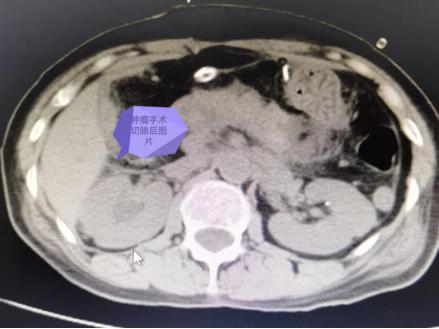

于是,张奶奶来到了长沙进一步确诊,通过 B 超及 CT 检查发现,莫奶奶肚子里长了一个足球大小的肿瘤,压迫影响到了胃,因此,张奶奶才腹胀明显;肿瘤越长越大,上顶到膈肌上了,出现了呼吸困难!于是,经过多学科讨论,任斗教授和普外科曾晓晨主任赶紧决定为其实施手术切除治疗。经过周密的术前准备,腊月 25,通过长达 8 小时的手术,奶奶的巨大肿瘤终于被完整的剥离切除了,这一称重,足足 10 斤!当切下来的肿瘤摆在家人面前的时候,家属也难以置信!